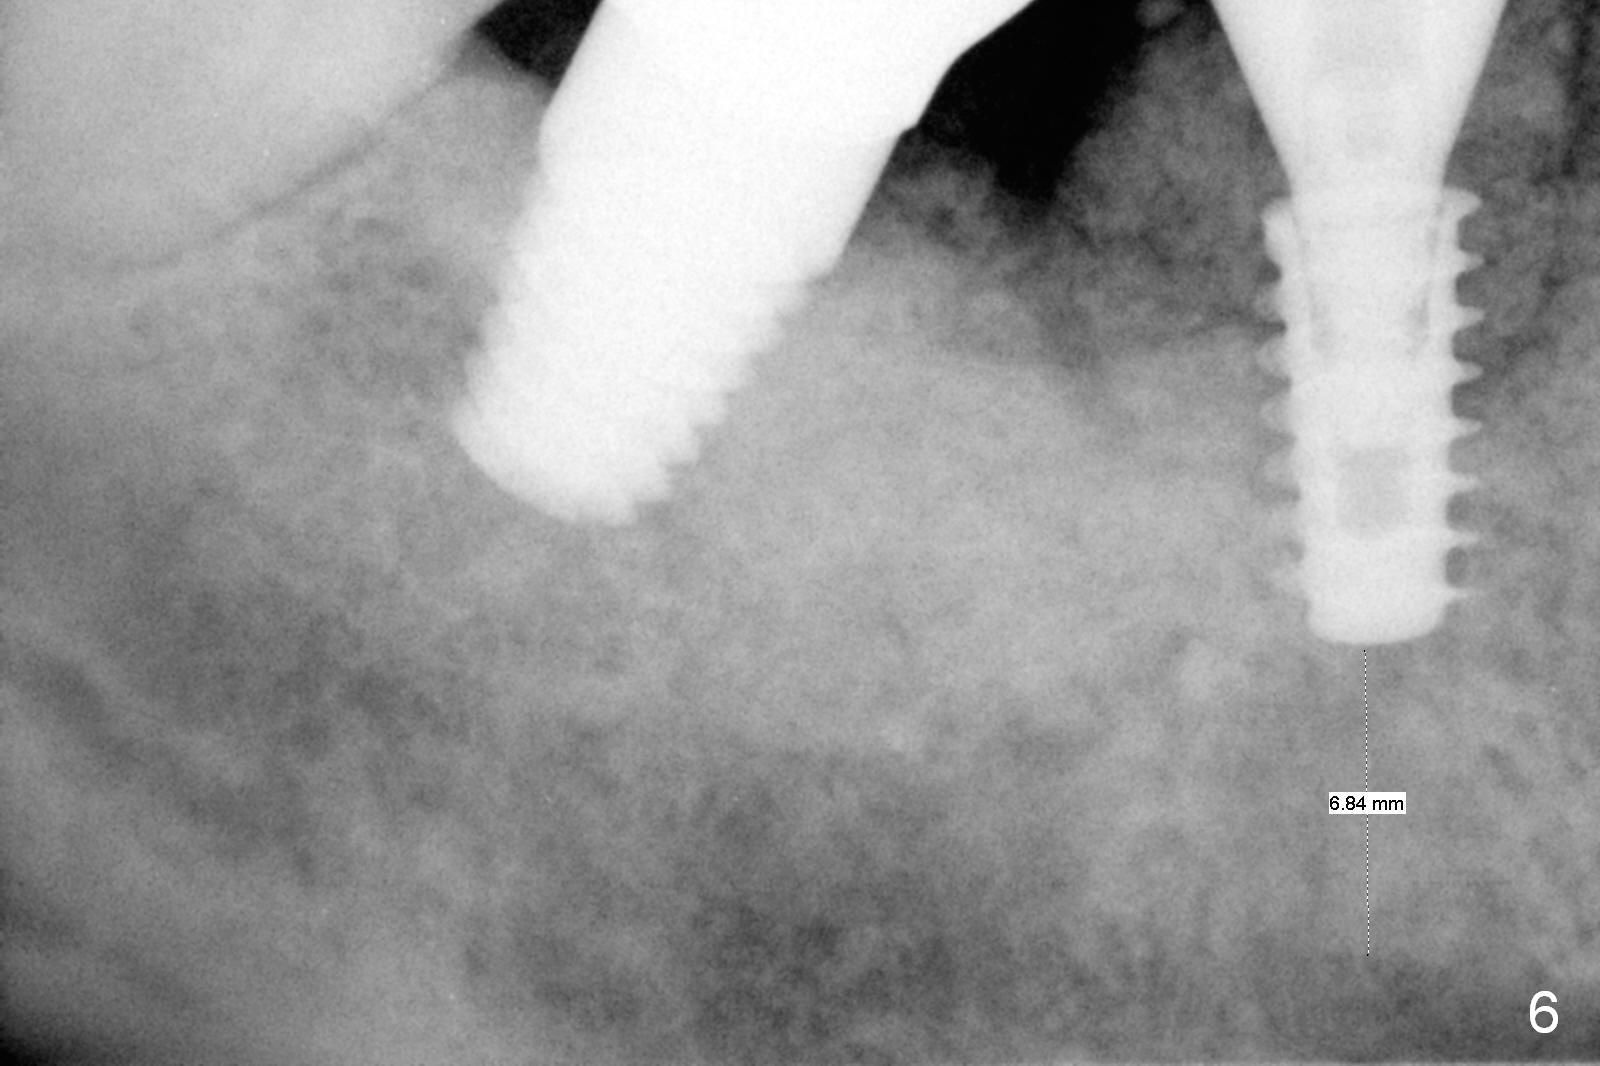

Extraction shows the large distal socket (Fig.1 D) and the thin and low septum (*) of the tooth #30. After Magic Split test confirms hard bone, osteotomy is initiated with 1.6 mm pilot drill with 11 mm stopper (Fig.2); there is 2.7 mm distance to the Inferior Alveolar Canal. Following Marking Bur, a 4.8 mm Magic Drill is used to finish the osteotomy with difficulty because of hard bone and ineffective local anesthesia due to infection. A 5x9 mm "dummy" implant is placed to determine the placement level relative to the distal crest (Fig.3 *). After removal of the dummy implant, an authentic one with the same dimension is placed with packing abundant allograft (.5-1.5 mm) and Osteogen (Fig.4 *); it appears that 4 to 5 threads (fins) of the implant (arrowheads) are engaged to the native bone for primary stability (>40 Ncm). Later more bone graft is placed distally (Fig.5 arrow). With the short implant placed not so deep, there is 6-7 mm clearance from the underlying canal (Fig.6). The patient is doing well 7 days postop (Fig.7). He feels that the provisional is too bulky buccally for the first 2 days postop. The buccal margin will be trimmed in another 2 weeks (dashed line). The patient in fact masticates on the right side postop. By the time he returns for provisional revision 1 months 10 days postop, he has mild pain. There is food entrapment. The provisional and the abutment are slightly loose, whereas the implant is stable with healing socket (Fig.8). A healing abutment is placed. The implant appears unstable nearly 5.5 months postop. The gap between the bone and implant seems to be large (Fig.9). The implant should have been larger and longer for fast healing. A healing screw is used instead. The site heals 10 months postop with an increase in bone density around the implant (Fig.10.) Prior to cementation of the final crown, the abutment is minimally exposed (Fig.11 (6.5x5.7(3) mm)). In fact the abutment screw becomes loose 2 months post cementation (1 year postop); it appears that crown/implant ratio is unfavorable (Fig.12). The implant is slightly placed mesially (cantilever). The patient cannot chew on the left. The tooth #19 is periodontally affected and the tooth #18 is missing. When bone loss is severe, the implant should be as large as possible and preferably tissue-level. The abutment screw is re-loosening 1.5 years post cementation (4 months post #19 socket preservation, Fig.13). The crown/implant ratio at #31 is more favorable than that at #30 (compare black lines). The crown at #31 has large contact area with the tissue-level implant (external), whereas the contact between the abutment and the bone-level implant is much less (internal). To prevent the abutment screw re-loosening (turning) in function, a screw driver (Fig.14 D) will be buried inside the crown/abutment after the screw is retightened. Make sure that the driver is in the middle of the access hole. Section the driver in situ obliquely (Fig.15); flat sectioning allows the driver to turn with the abutment screw in function. After insertion of plumber tape around the sectioned screw driver, use composite to fix the driver in place and seal the access hole (Fig.16). Occlusal check suggests weak link between the abutment and bone-level implant at #30.